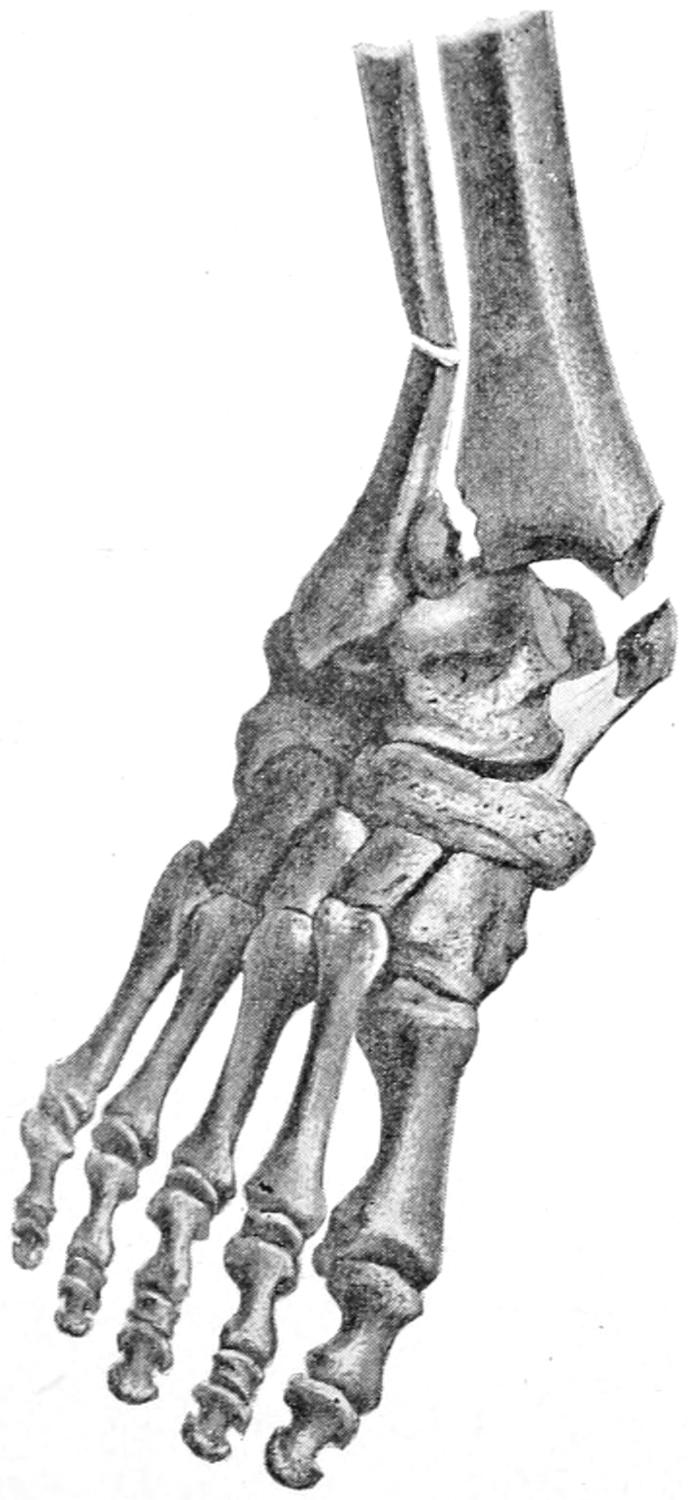

FRACTURES 479